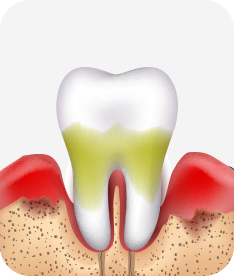

치아신경 염증

충치가 심해져 치아 뿌리까지 신경 염증이 발생함

치주염 단계별 증상

치은염 (초기~중기)

치아 주위의 잇몸이 붉게 부어 있으며, 칫솔질 등을 할 때 피가 남.

스케일링 주기의 조절이 필요할 수 있으며, 올바른 칫솔질을 시행하여야 함.

치주염 (중기~말기)

주기적으로 잇몸이 붓고 피가 나며, 욱씬하거나 우리한 통증이 나타남.

치주치료 및 정도에 따라 치주수술(잇몸수술)이 필요함. 향후 관리 정도에 따라 3~6개월 간격으로 내원하여 유지치료를 시행하여야 함.